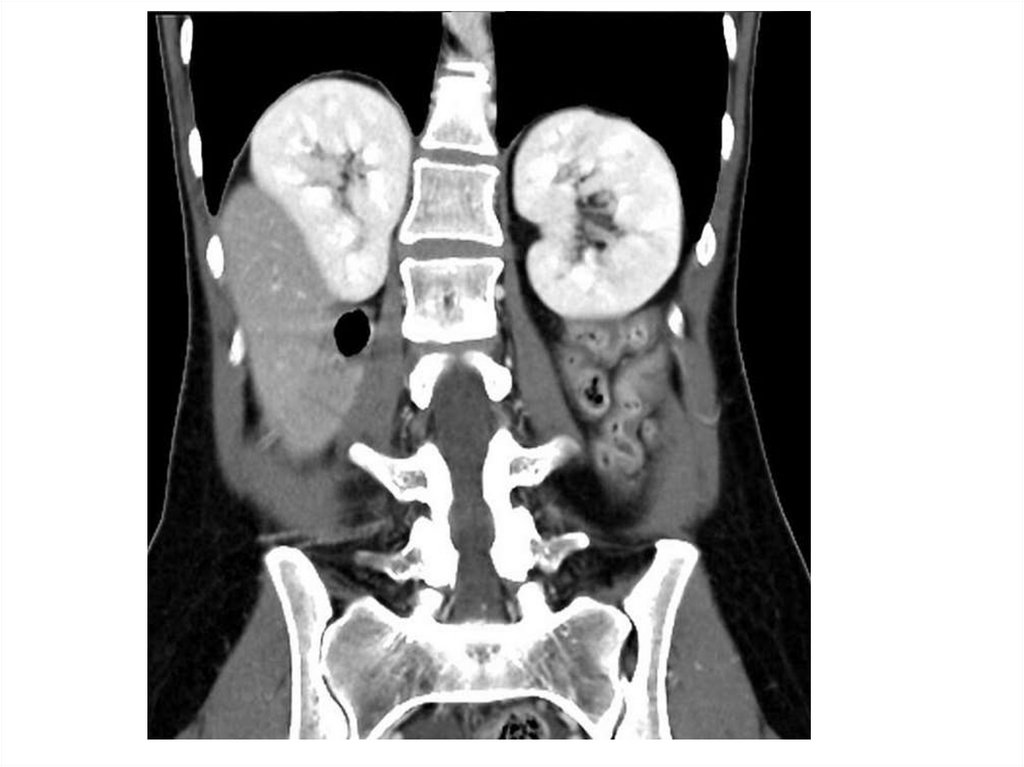

Назовите

• Вид исследования

• Область исследования

• Патологию